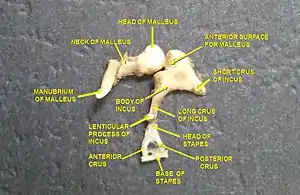

L'enclume a une forme de molaire constitué d'un corps cubique et de deux branches. L'une supérieure et horizontale forme la branche courte, et l'autre inférieure et verticale forme la branche longue

Corps de l'enclume

Le corps de l'enclume se situe dans le récessus épitympanique. Il a grossièrement la forme d’un cube aplati de dehors en dedans. Sa face antérieure concave porte la facette articulaire du corps de l'enclume qui répond à la facette articulaire du marteau pour former l'articulation incudo-malléaire.

Branche courte de l'enclume

La branche courte de l'enclume (ou branche courte de l'incus ou courte apophyse de l’enclume ou branche horizontale de l’enclume) est un prolongement osseux en forme de cône aplati de dehors en dedans. Elle s'étend horizontalement en arrière du corps de l'enclume. Son sommet, qui correspond à l'extrémité postérieure s'appuie sur l'échancrure située à l'angle inférieur de l'orifice antérieur de l'aditus ad antrum,

Branche longue de l'enclume

La branche longue de l'enclume (ou branche longue de l'incus ou longue apophyse de l’enclume ou branche verticale de l’enclume) est un prolongement osseux plus long et plus étroit que la branche courte. Elle descend verticalement du corps de l'enclume, en dedans et en arrière du manche du marteau, puis son extrémité inférieure se recourbe en dedans avant de former le processus lenticulaire qui porte la facette articulaire du processus lenticulaire (ou processus lenticulaire de l'incus ou apophyse lenticulaire de l’enclume ou os lenticulaire ou osselet de Sylvius) qui répond à la cavité glénoïde de l'étrier pour former l'articulation incudo-stapédienne .

Place de la chaine des osselets dans l'oreille  Dissection d'une chaine articulaire, avec l'incus au centre

Dissection d'une chaine articulaire, avec l'incus au centre